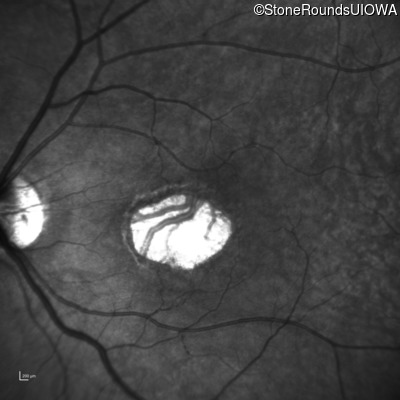

This 59 year old woman first noticed a reduction in her visual acuity and photophobia in her late teens.

| AD Cone and Cone Rod Dystrophy | GUCA1A | Glu155Gly GAG>GGG | AD |